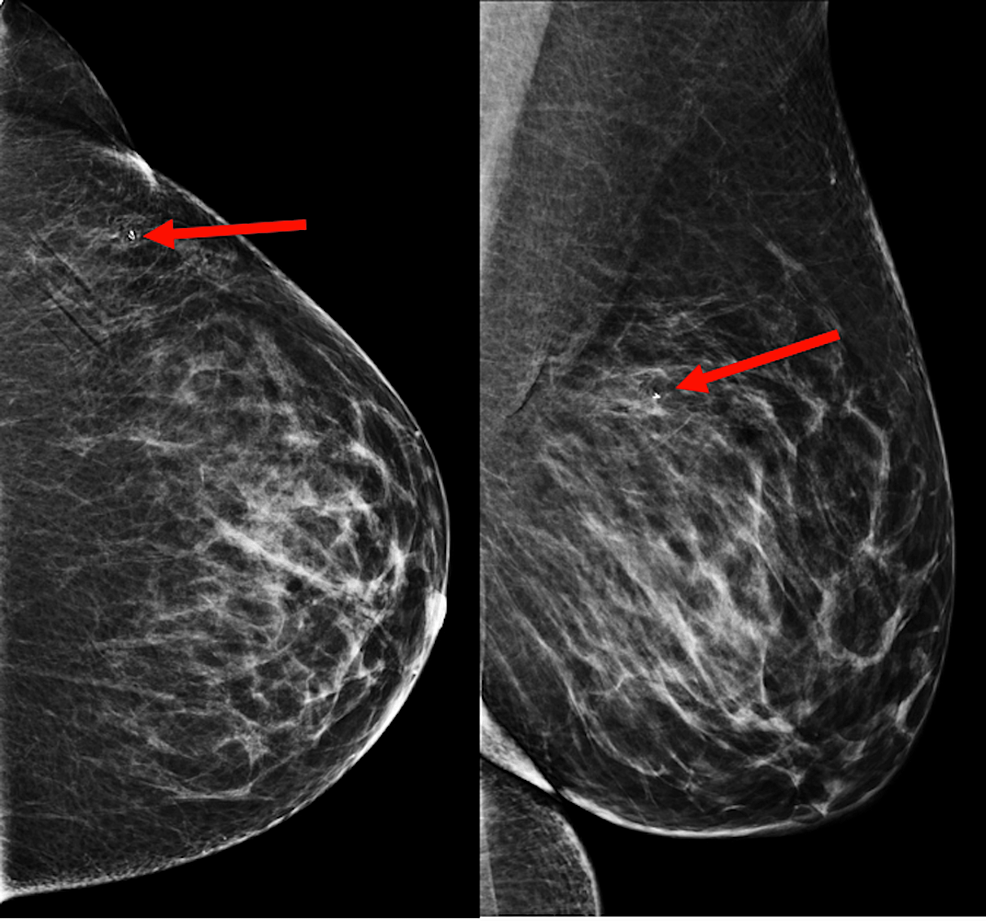

Titanium Markers for Breast Biopsy Uses and Side Effects Titanium Placed In Breast A breast marker is a tiny titanium or stainless steel marker, smaller than a sesame seed. The hydromark® line of breast tissue markers, also manufactured by mammotome, offers options for a titanium or stainless steel clip embedded in hydrogel (fig. The diagnosis was atypical ductal hyperplasia. Breast biopsy markers are placed during a breast. I have already had one biopsy. Titanium Placed In Breast.